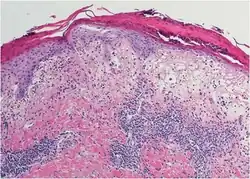

Histopathology

Histopathology show distinct changes in vacuoles and Civatte bodies in all levels of the epidermis.[2] The is melanin incontinence and neutrophils and eosinophils.[2]

Melanin incontinence -

Basal vacuolation